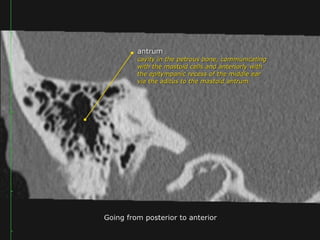

 The antrum is a large aircell superior and posterior

to the tympanic cavity and connected to the

tympanic cavity via the aditus ad antrum.

 It is surrounded by smaller mastoid aircells.